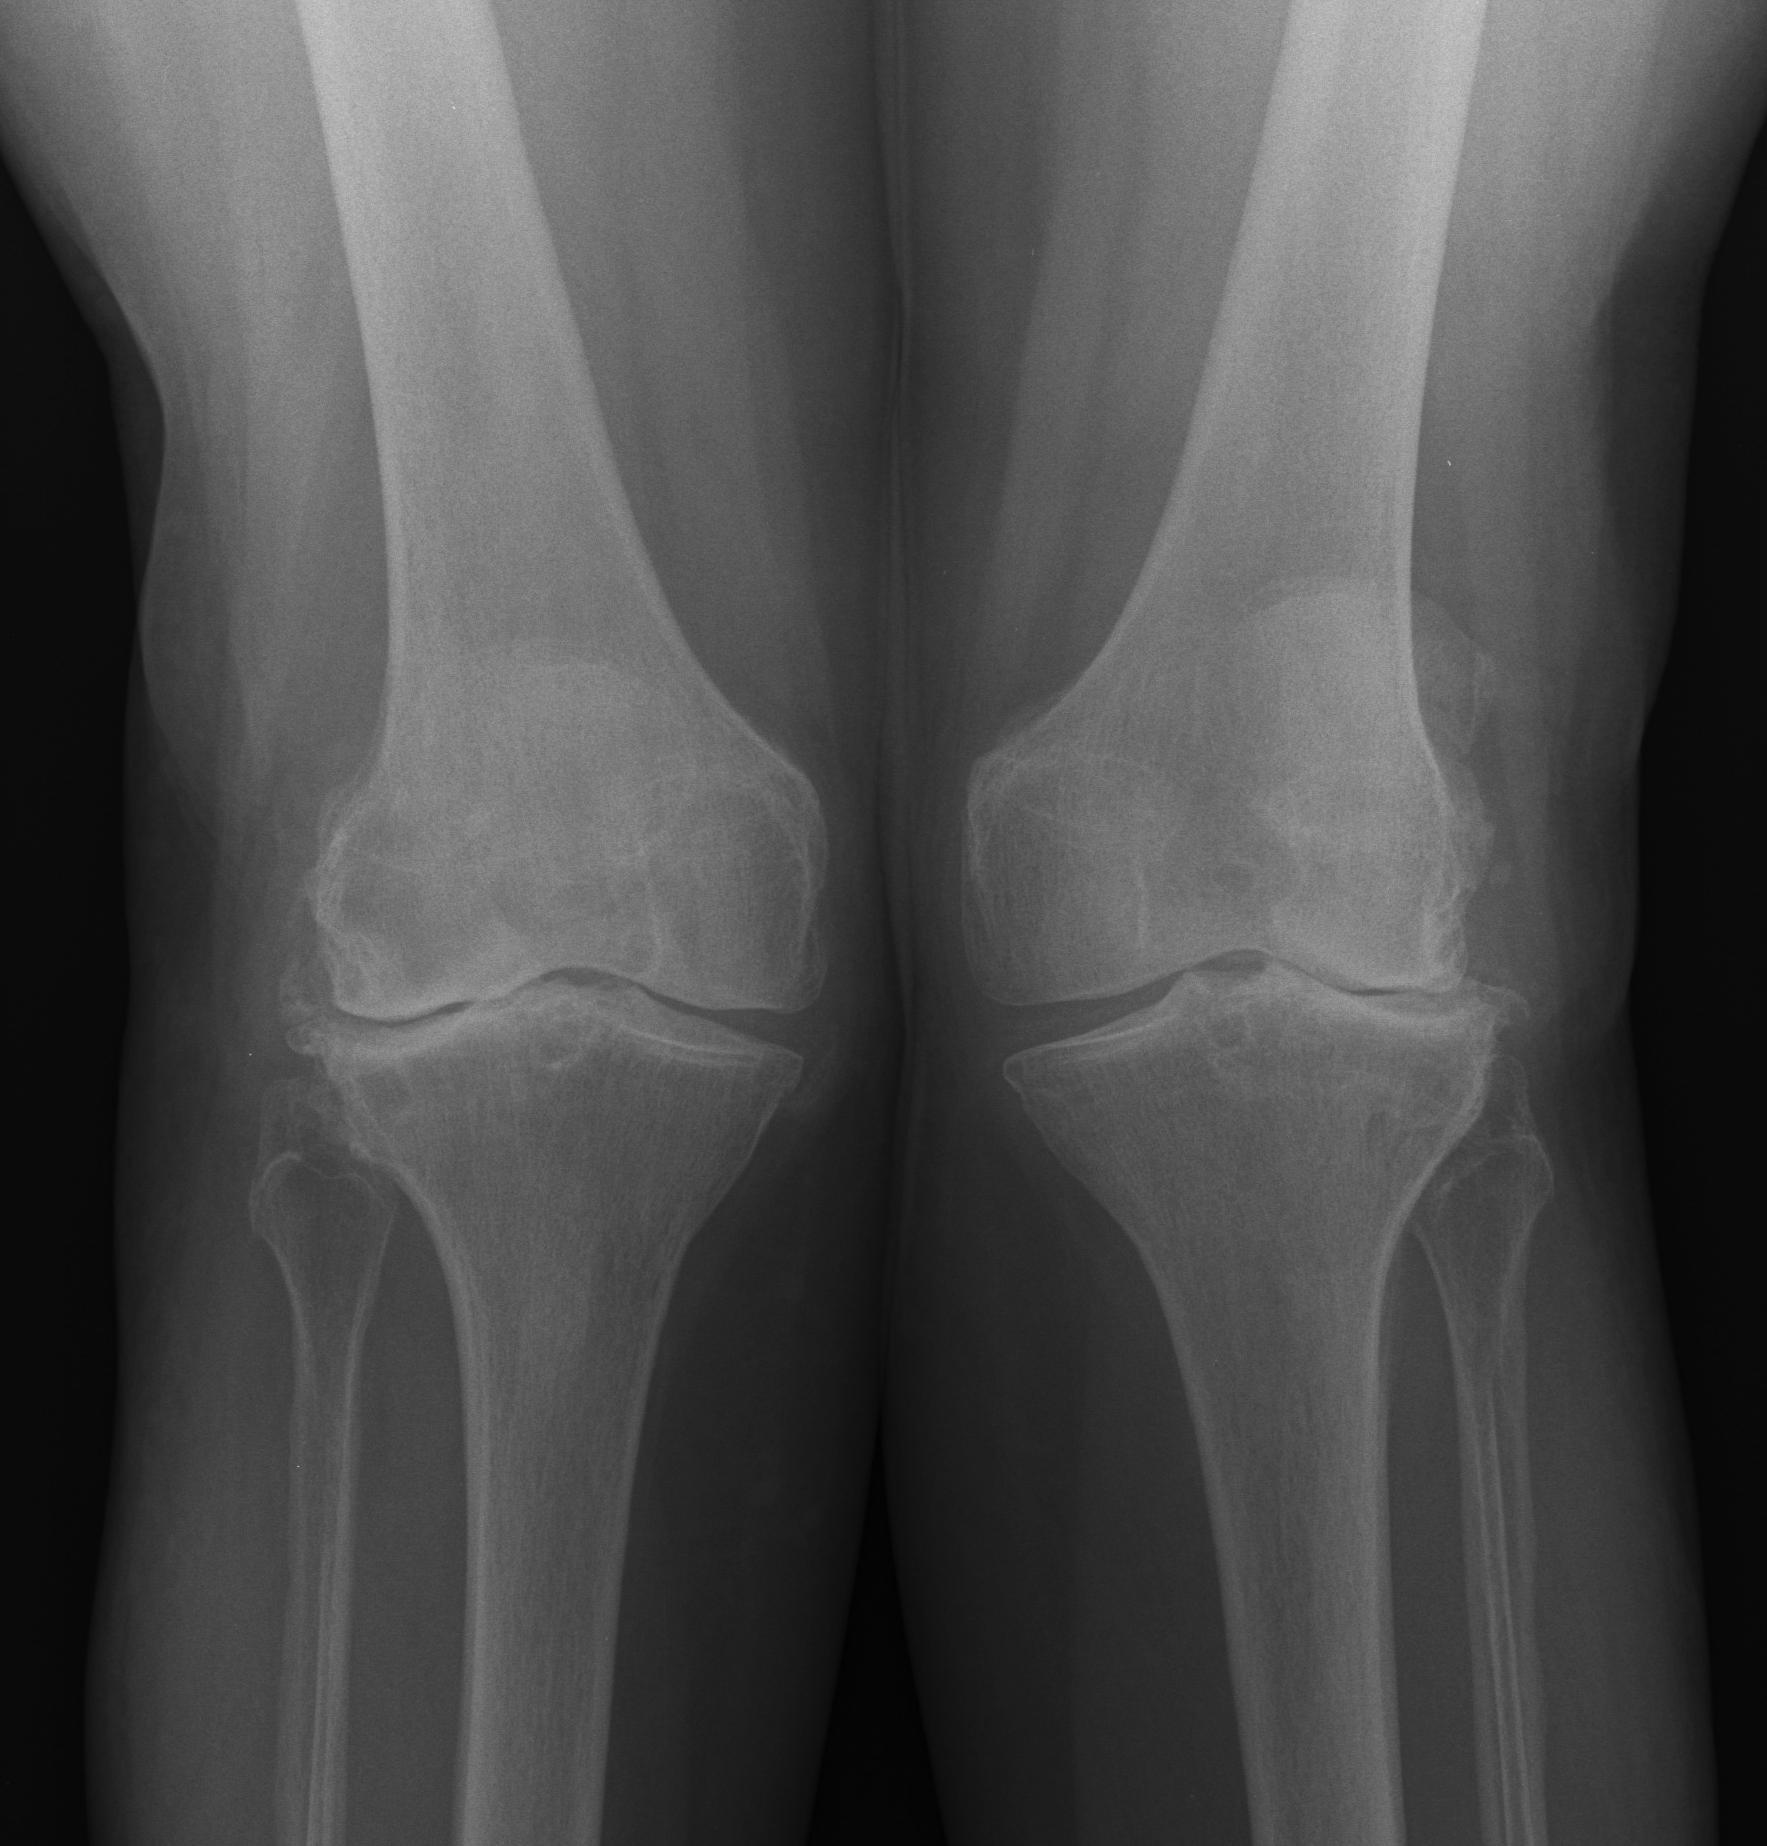

TKR Moderate Valgus OAValgus Malalignment

TKR Bilateral Valgus OA